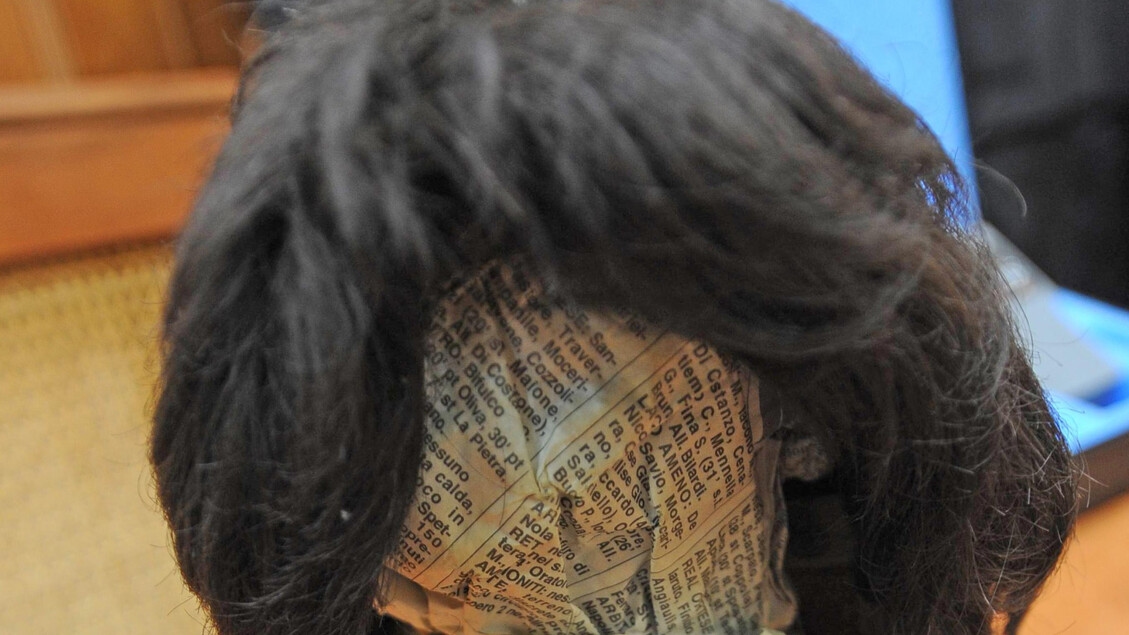

Una mini-stampante 3DIl dispositivo in questione è un tubicino, dotato di un’apertura ad un’estremità da cui è possibile far fuoriuscire l’idrogel a base di acido ialuronico. Di fatto si tratta di una mini-stampante in 3D, la cui attività può essere controllata (sebbene al momento solo manualmente) e che è compatibile con gli interventi di laringoscopia in sospensione. Vale a dire che il device è così piccolo (20 mm di lunghezza per la precisione, con la biostampante in cima al tubicino di appena 2,7 mm di diametro) che non intralcia gli interventi che prevedono l’uso di un laringoscopio associato a un microscopio. Questo piccolo strumento è controllato in maniera precisa e ripetibile, puntualizzano i suoi ideatori, grazie all’uso cavi inseriti in un supporto che ne regolano la tensione e a una sorta di joystick con collegamento wireless.